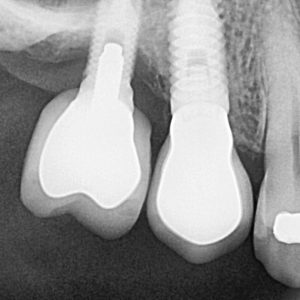

La implantología oral es una especialidad de la odontología que se encarga de la colocación de implantes dentales, dispositivos de titanio que sustituyen la raíz del diente perdido. Estos implantes se integran con el hueso maxilar en un proceso llamado osteointegración, proporcionando una base sólida para la colocación de una corona dental que imita la apariencia y funcionalidad de un diente natural.

1. Evaluación y planificación: Se realiza un estudio detallado con radiografías y escáneres 3D para determinar la viabilidad del tratamiento.

2. Colocación del implante: Bajo anestesia local, el implante se inserta en el hueso maxilar o mandibular.

3. Cicatrización y osteointegración: Durante unos meses, el implante se fusiona con el hueso, asegurando su estabilidad.

4. Colocación de la corona: Finalmente, se coloca la prótesis dental personalizada sobre el implante.